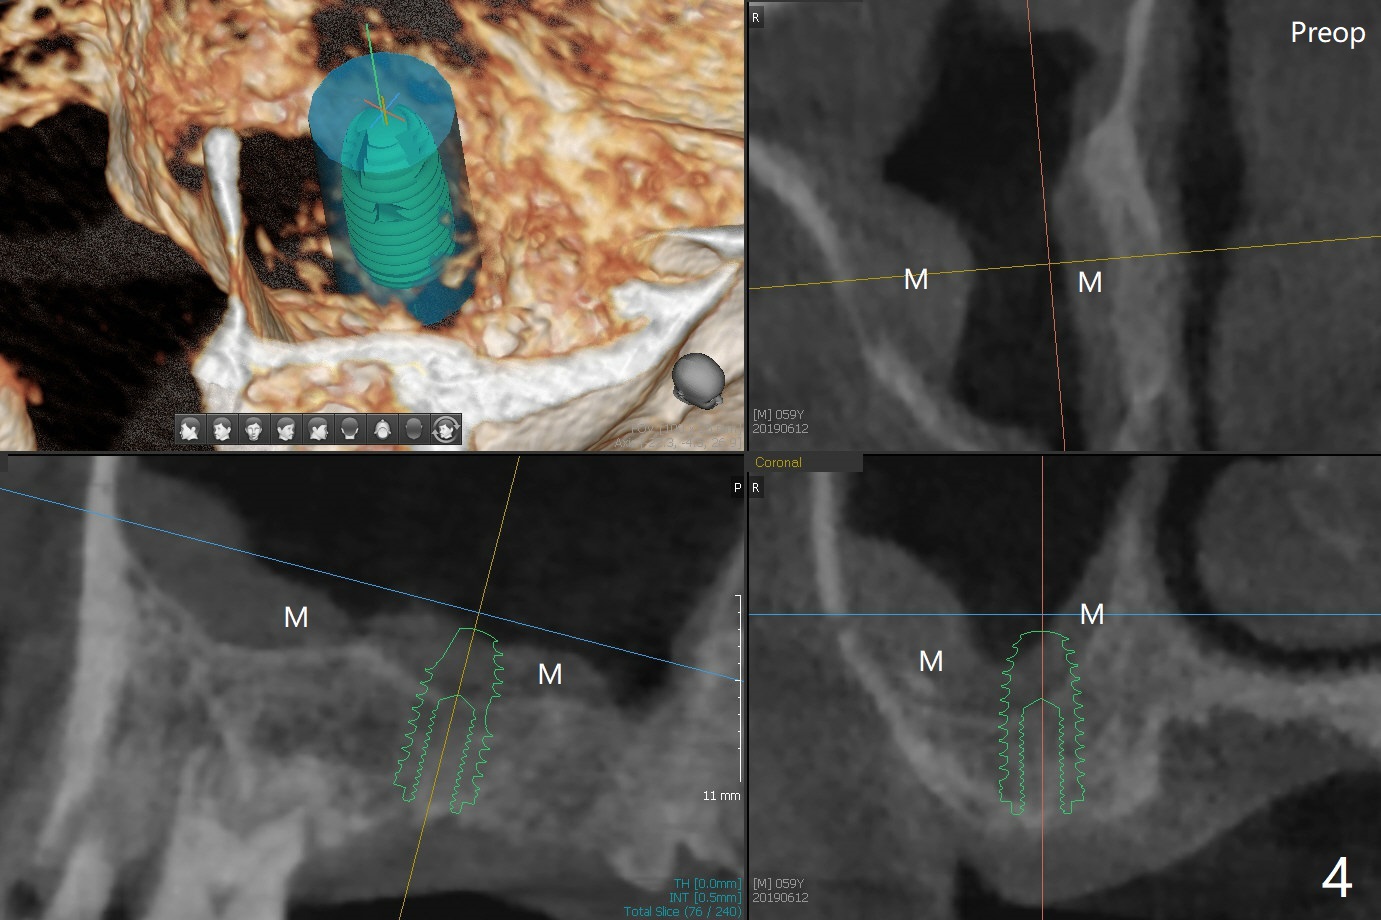

Two things happen immediately before this surgery. A SM implant is found to fail related to bruxism and poor oral hygiene, ~ 5 years in function; a UF implant will be used instead. DIO Sinus Approach Kit has not been autoclaved; therefore the free-hand one has to be used with caution. In fact the procedure goes on apparently smoothly in spite of the fact that the patient with medical knowledge is nervous about the risk of sinus lift. After 4.0x8.5 mm Neo Navi drill with 12 mm offset, the 3.6 mm sinus safety drill is used from 7 to 9 mm in length, followed by water balloon, PRF membranes (x2) and mixture of autogenous bone graft and allograft and 4.5x10 mm dummy implant (Fig.1). The definitive implant is placed with satisfactory stability (Fig.2), but a 6.5x7(4) mm healing abutment is close to the mesial crest (*). The former is reloaded following 6.0 mm Bone Profile Drill (Fig.3) and then is changed to a 6x6 mm IS one. The patient reports nasal hemorrhage immediately returning home, but there is no similar episode a few hours later. Re-analysis of preop (Fig.4) and immediate postop (Fig.5) CT shows that water balloon technique in fact swells the sinus membrane (M) instead elevating it. It is safe to place more bone graft (Fig.5 *). There is pain when the 6x6 mm healing abutment is being removed nearly 5 months postop (Fig.6.7). The patient complains of mild sinus discomfort, although panoramic X-ray does not show abnormality (Fig.8). He will return for recheck for implant stability (low bone density) before impression 2-4 months later.